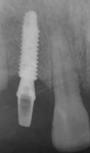

Cone beam examination revealed mesio distal space: 8mm , Bone thickness<6mm and Available bone height: 15mm (Figure 5)

Figure 5 Cone beam + sagittal sections.

The low bone volume represented a real surgical difficulty in placing a standard diameter implant.